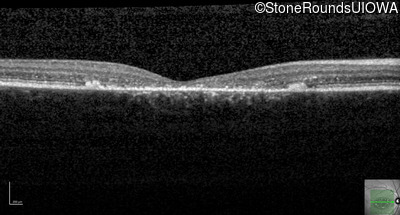

Optical Coherence Tomography - Left - 20/150

Exemplar / OCT Stack